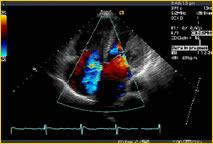

Digisonics offers a Web-based system for configurable, multimodality reporting. Rated 2008 Best in KLAS for cardiology, the Digisonics image management and reporting systems combine high-performance image analysis, professional reporting, an integrated clinical database, a powerful PACS image archive and exceptional solutions for remote connectivity into one system.